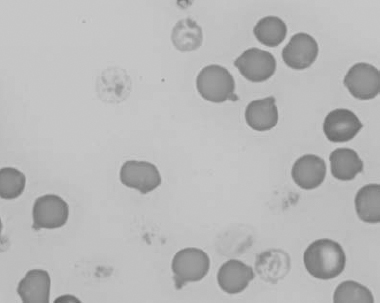

Figure 1.10 Canine blood film showing echinocytes I (also see color section).

Figure 1.11 Canine blood film showing echinocytes III (also see color section).

Figure 1.12 Feline blood film showing echinoelliptocytes (also see color section).

Figure 1.13 Canine blood film showing Heinz bodies and ghost cells due to oxidative damage. There are also several polychromatophils (also see color section).

Figure 1.14 Canine blood film stained with new methylene blue, to demonstrate Heinz bodies (also see color section).

Figure 1.15 Canine blood film showing keratocytes and schizocytes (erythrocyte fragments) due to fibrin strand injury. A codocyte and a polychromatophil also appear in the field (also see color section).

Figure 1.16 Feline blood film showing Mycoplasma hemofelis organisms (hemobartonellosis). Organisms are not always visible in blood smears from infected cats (also see color section).

Figure 1.17 Canine blood film showing several macrocytes (also see color section).

Figure 1.18 Canine blood film showing a metarubricyte There is also a polychromatophilic macrocyte in the field (also see color section).

Figure 1.19 Canine blood film showing microcytic, hypochromic erythrocytes consistent with iron deficiency anemia. There are two polychromatophils in the field, indicating that the anemia is regenerative (also see color section).

Figure 1.20 Canine blood film showing two macrocytes with nuclear remnants (also see color section).

Figure 1.21 Bovine (calf) blood film showing marked poikilocytosis (normal?) (also see color section).

Figure 1.22 New methylene-blue-stained Canine blood film showing reticulocytes (also see color section).

Figure 1.23 Canine blood film showing rouleaux formation (also see color section).

Figure 1.24 Canine blood film showing spherocytosis and polychromasia due to immune-mediated hemolytic anemia (also see color section).

Figure 1.25 The red blood cell cytoskeleton.